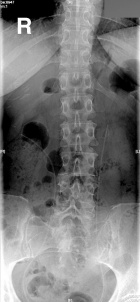

L.T. - 53 year old woman with left lower extremity and pelvic pain for two months

Zoom image: Radiological image Radiological image.